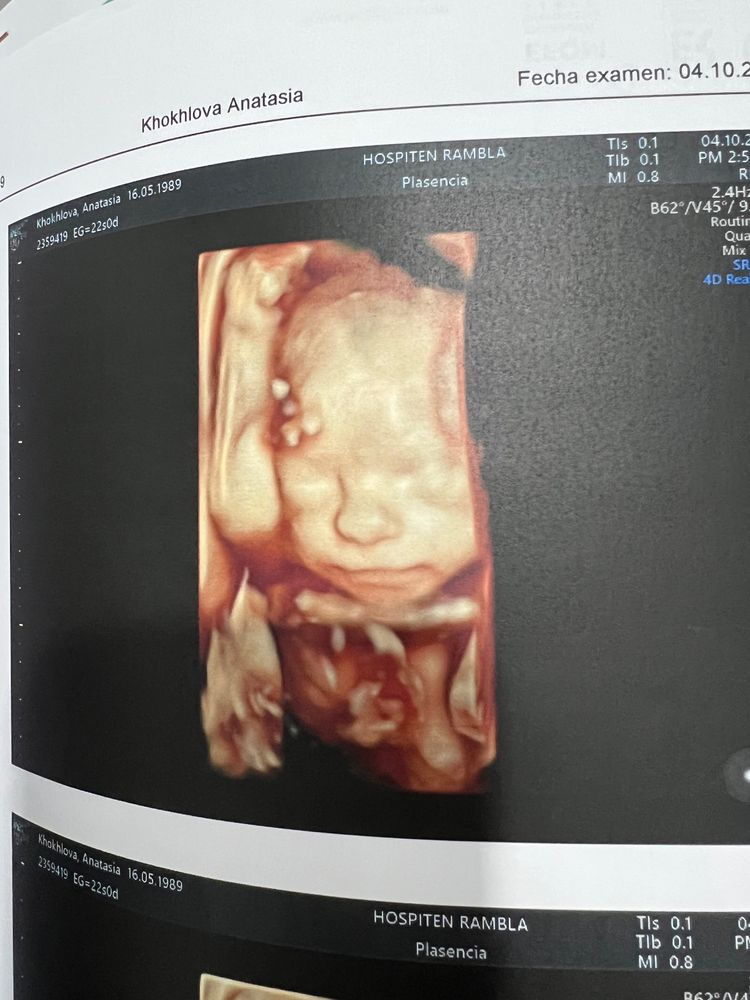

22 недели 5-ой беременности ✨

Была на обширном узи. Врач сказал «все прекрасно! Жду вас через год с новой беременностью» 😂😂😂

Изображение

Мне надо купить футболку с надписью «it's my last one. Ser